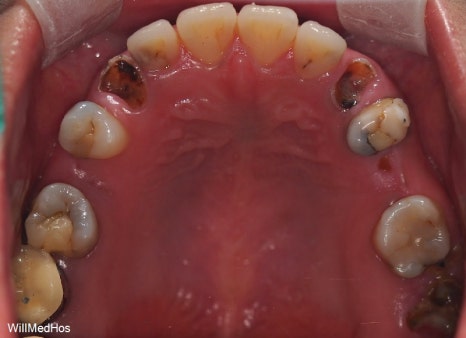

먼저 구강 사진 부터 보도록 하겠습니다.

이미 충치들과 염증으로 인해 치관을 다 없어지고 잔존 뿌리들만 겨우 남아있는 상태들의 치아들

염증으로 인하여 살리기 힘든 치아들도 다수 있었습니다

나이가 젊으신 분인만큼 최대한 살릴 수 있는 치아들은 살리고 임플란트 필요 치아들을 치료하는 방향으로 계획을 잡았습니다.

치조골이 소실 되어 있는 부분들은 뼈이식과 함께 진행 하였습니다.